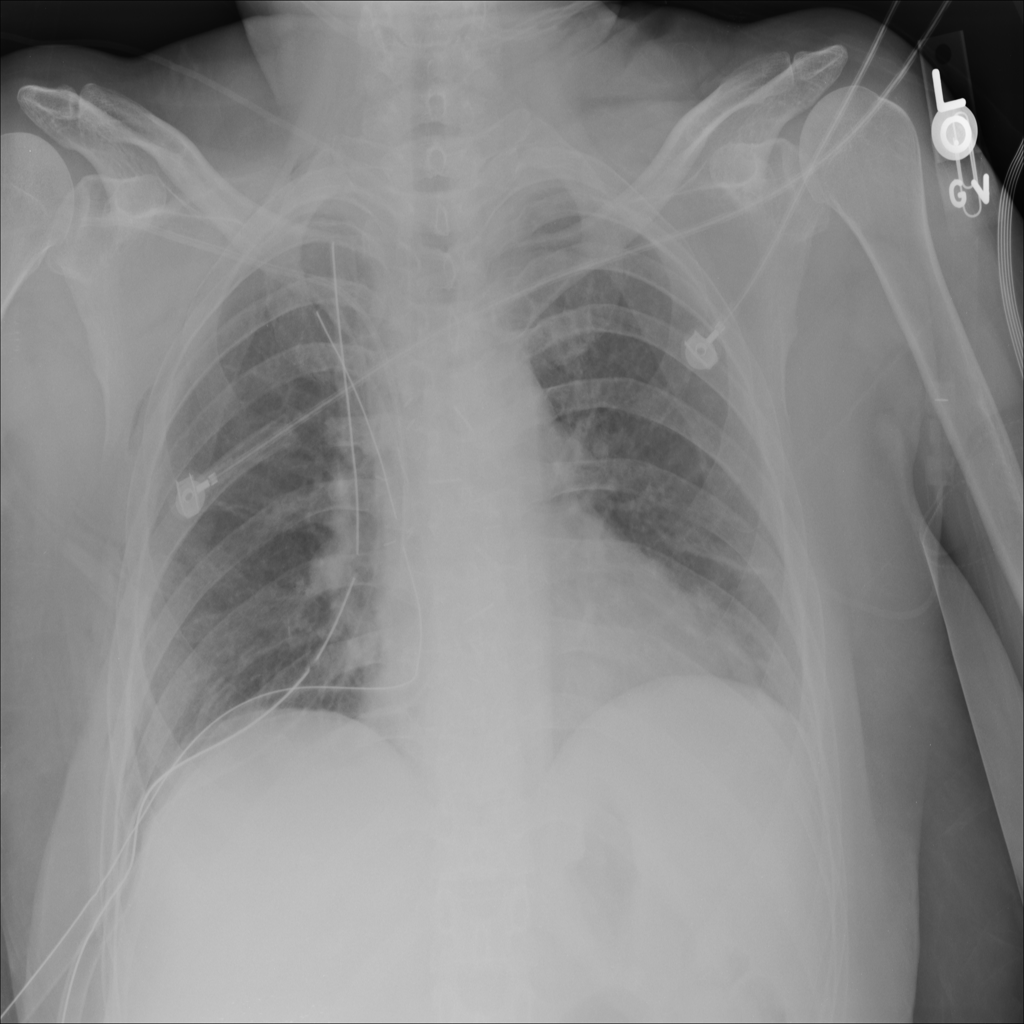

PAT-0E82 · IMG-000Emphysema

PAT-0E82 · IMG-000

AP